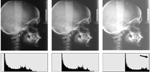

Morphing and warping: Part II. Halazonetis DJ. Am J Orthod Dentofacial Orthop. 1999 Jun;115(6):706-8. doi: 10.1016/s0889-5406(99)70098-3. PMID: 10358255

Morphing and warping. Part I. Halazonetis DJ. Am J Orthod Dentofacial Orthop. 1999 Apr;115(4):466-77. doi: 10.1016/s0889-5406(99)70074-0. PMID: 10194292